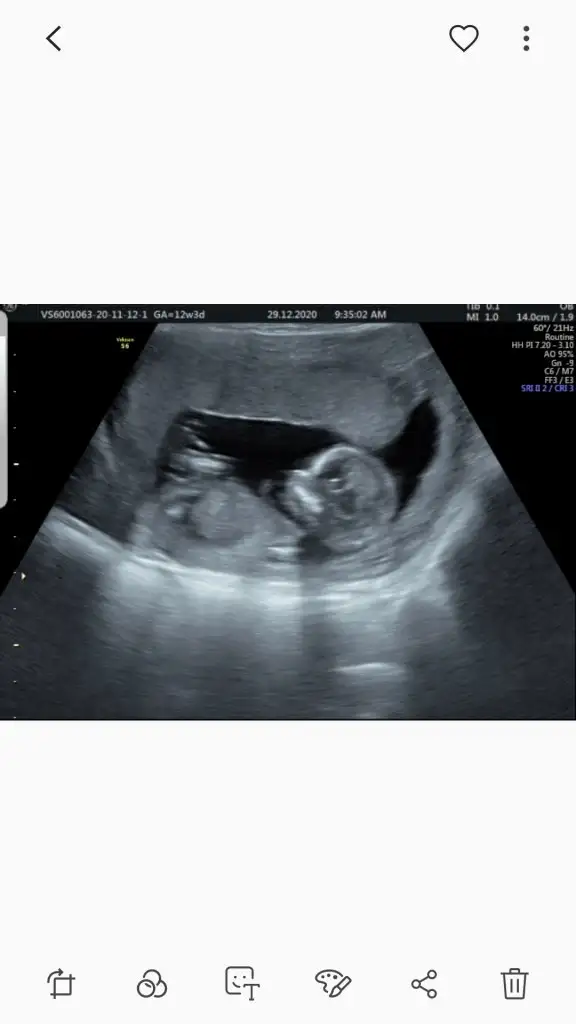

dr soylemeden siz gorun genital nub teorisi ( bebegin cinsiyeti)

12+0 benimde yorumlarmısın

Geçen hafta da bakmıştık doktor da sen de kıza benziyor demiştin Ikra meyra :) Ama bugün doktor erkeğe benziyor dedi tam belli olmuyor nubu tek ultrason fotoğrafı var bugünden ama bir denemek istedim bakalım bugün ne diceksin :)

Ölçümün hemen yanında nubu yüksek görünüyor 12+5 gore erkek görünüyor